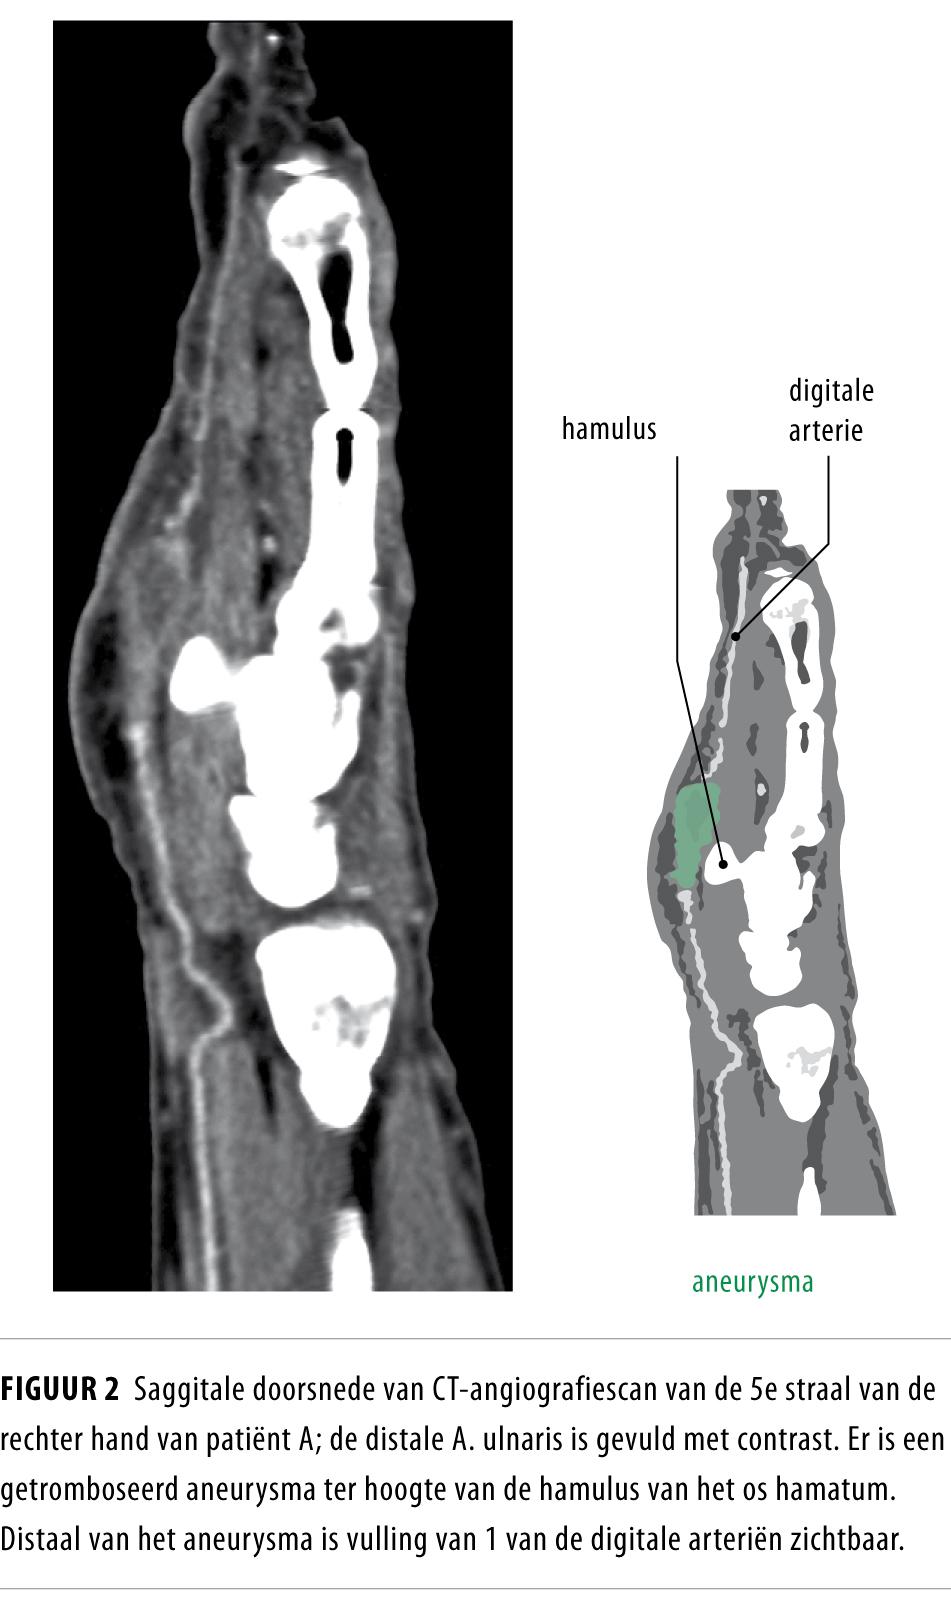

Aanvullend onderzoek met kleuren-dopplerechografie (figuur 1) en CT-angiografie (figuur 2 en 3) laat een occlusie van de A. ulnaris over een kort traject zien ter hoogte van de hamulus van het os hamatum. Ter plaatse is ook een aneurysmatische verwijding tot een diameter van 1,0 cm zichtbaar. De diagnose ‘HHS’ wordt hierdoor ondersteund.

Figuur 2

CT-angiografie is een alternatief voor conventionele angiografie, omdat hiermee, naast de bloedvaten zelf, ook extraluminaal gelegen structuren in beeld gebracht kunnen worden die aanleiding tot klachten kunnen geven.10 Hierbij kan gedacht worden aan compressie van de A. ulnaris door bijvoorbeeld een fractuur van het os hamatum of aan compressie door een schwannoom dat uitgaat van de naastgelegen N. ulnaris.